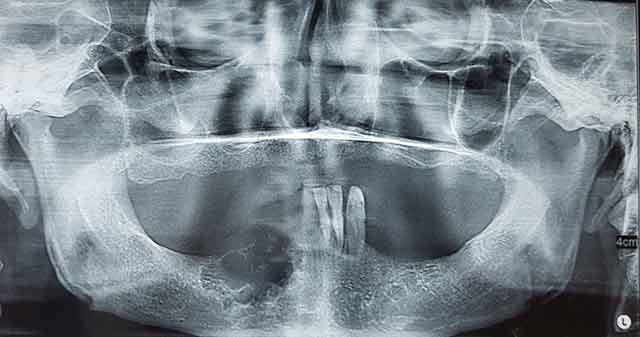

![]() Fig 3 : Radiographie panoramique montrant une image radioclaire multi-géodique. |

La tuméfaction était recouverte d’une muqueuse d’aspect normal, indurée à la palpation avec sensation de soufflure de la corticale osseuse vestibulaire par endroit. La ponction à l’aide d’une seringue à usage unique 10cc n’avait rien rapporté. La radiographie panoramique montrait une lésion radioclaire bien limitée, cloisonnée en nid d’abeilles s’étendant de la région de la 42 à la 47, et en rapport avec le foramen mentonnier (Fig 3).

L’améloblastome folliculaire se présente le plus souvent en image polygéodique, comme dans le cas présenté. En présence de dents, on peut retrouver des résorptions radiculaires.La prise en charge de l’améloblastome est compliquée par la nature de la tumeur. Elle doit être limitée du fait de la bénignité de l’améloblastome mais exhaustive pour éviter une éventuelle récidive. Le traitement de l’améloblastome peut être chirurgical ou non. Les thérapeutiques non chirurgicales utilisent la radiothérapie combinée ou non à la chimiothérapie. Les contres indications et l’efficacité assez controversée de ces thérapeutiques limitent leur utilisation aux patients chez lesquels la chirurgie est contre-indiquée (5).